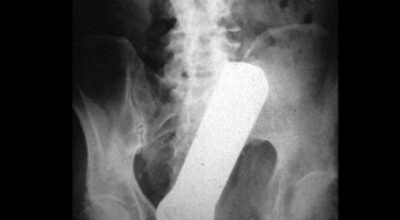

Esta recopilación de imágenes recoge alguna de las situaciones más estrambóticas que se han podido dar en una sala de rayos X. Todas ellas tienen algo en común: Son objetos extraños para el cuerpo humano que, de alguna manera han encontrado una vía de entrada, pero se han perdido a la hora de encontrar la de salida.

Muñecas de juguete descabezadas, botellas, armas, frascos, botes de plástico, teléfonos y hasta una cinta de casete pueden encontrarse en esa suerte de “punto limpio” al que ha quedado reducido el interior de los afectados.